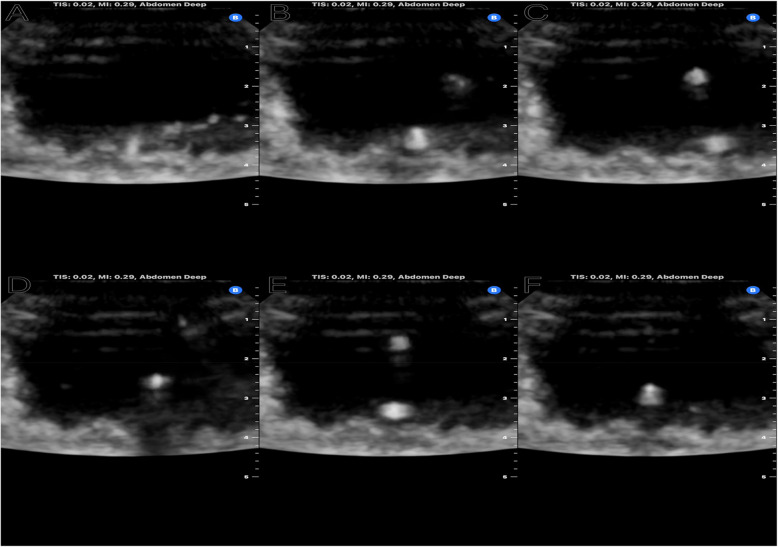

Methods: We conducted a simulation study using five different brands of ureteral stents in an ex-vivo porcine bladder model. We measured the mean grey intensity to quantify echogenicity of each stent. After comparing the echogenicity of individual stents, we grouped stents based on materials and diameters and performed T-tests.

Results: We established that ureteral stents can demonstrate good visibility inside porcine bladder under ultrasound. Upon further investigation, we found that diameter is the most important variable in determining the measured echogenicity of ureteral stents. 8 Fr ureteral stents have higher measured echogenicity than the Sensor wire and 6 Fr stents. Stent materials also play a role in the measured echogenicity of ureteral stents. With the same diameter, silicone is measurably more echogenic than polyurethane.